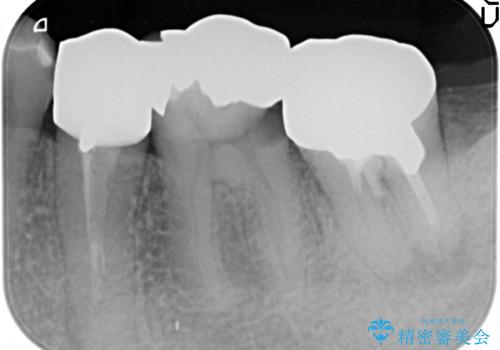

- 左下の奥歯がズキズキ痛むので診て欲しいといらっしゃった方の症例です。他院では5番目と7番目の歯を抜歯してインプラントと言われたが、出来れば歯を残したいとのことでした。

痛みの原因は6番目の虫歯であること、5番目、6番目の歯は歯茎より深い虫歯であり現状では保存が難しいことを説明した上で、歯を挺出させる部分矯正と歯茎を下げる歯周外科を行いました。